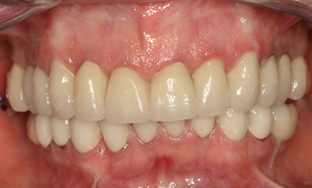

With dental implants at the back of the mouth, we were able to provide her with functional teeth which were solid and fixed. This eliminated any need for removable dentures, with crowns being used at the front of the mouth to stabilise, strengthen and improve the teeth. She is now seen on a regular basis for follow up to ensure that her mouth remains healthy.

She is delighted with the end result.